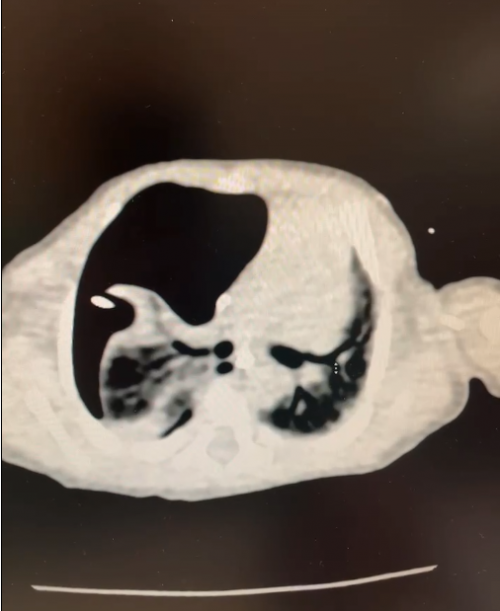

患儿术前CT示右侧大量气胸由于患儿病情危重无法耐受转运,只能当地手术,广州医科大学附属妇女儿童医疗中心立即启动应急响应机制。曾嘉航主任和徐颖怡主任制定了精细化治疗方案,携带儿童专用器械星夜驰援。抵澳后,穗澳专家马上完成术前联合会诊。鉴于患儿体内放置两条胸腔引流管仍无法解决张力性气胸的问题,且无法耐受转运到手术室手术,澳门仁伯爵综合医院儿科总负责人黄凤欣主任当机立断,决定直接在监护室床边开胸探查。